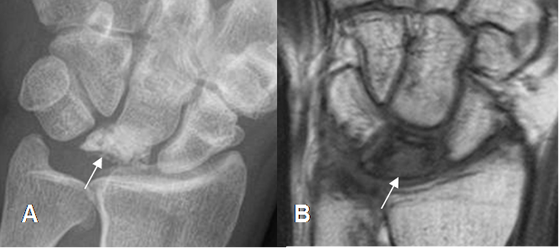

En la varianza ulnar positiva, la ulna es mas larga y se asocia con síndrome de impactación (Fig 13)y en la negativa, la ulna es mas corta, asociándose a enfermedad de Kienböck.(Osteonecrosis del semilunar). (6). (Fig 14).

Fig 14. Varianza ulnar negativa.

A: Rx AP y B: RM coronal en T1. Varianza ulnar negativa, con extremo de la ulna, mas corto que el radio.

Fig 15. Osteonecrosis del semilunar.

A: Rx AP. Pérdida de la configuración y aumento en la densidad del hueso semilunar.

B: RM coronal en T1. Semilunar hipointenso, por la presencia de necrosis.